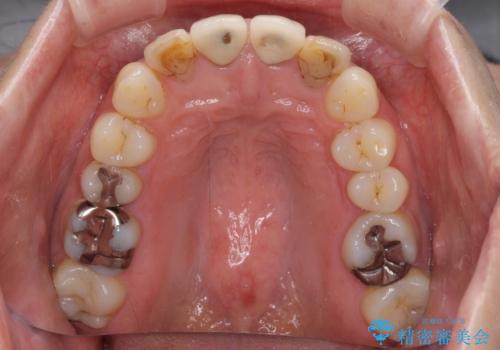

- 前歯のクラウンの変色や歯の変色を気にして来院された患者様です。

グラスファイバーを用いた土台により歯質を強化した上で、オールセラミッククラウンにて補綴することとしました。

統一感があり、歯肉ラインもきれいに整い、清潔感溢れる口元に仕上げることができました。